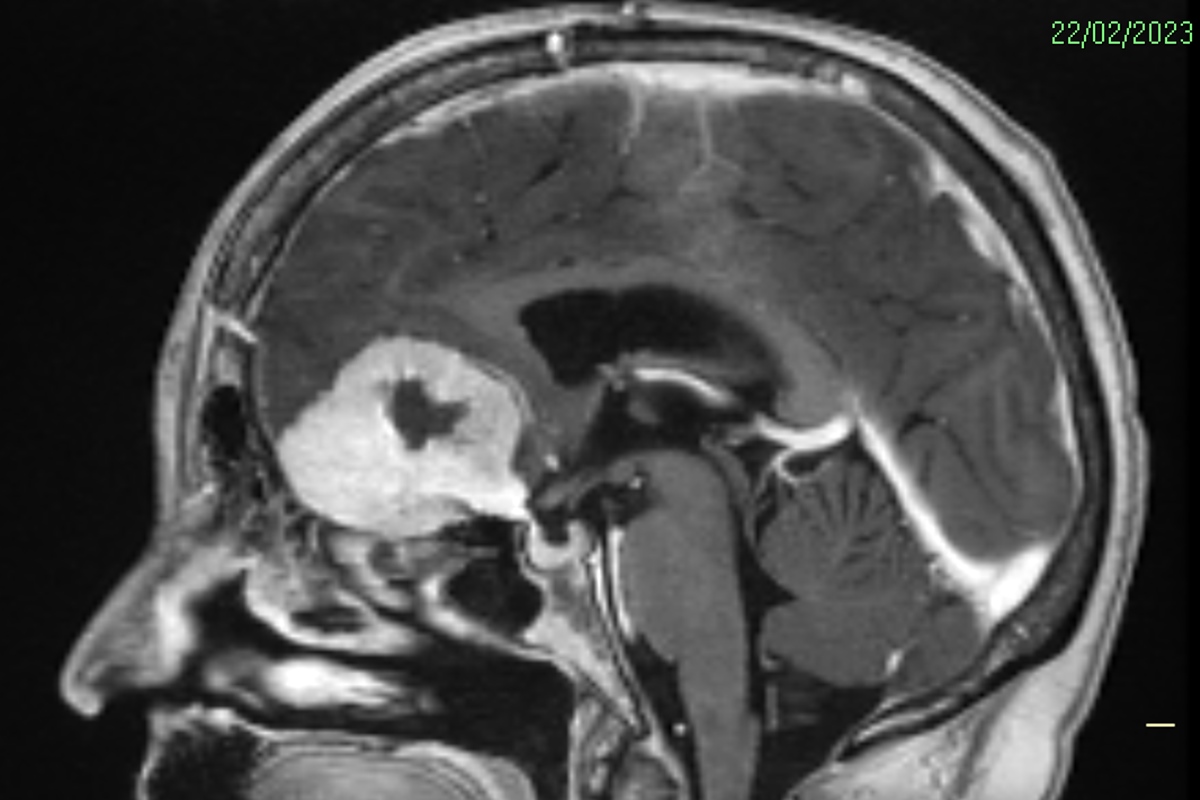

Imagem de tomografia de Doreen Adams mostra o tumor (massa branca) antes da cirurgia